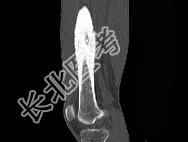

- 单项选择题男,23岁, 左大腿远端疼痛,夜间明显, 服阿司匹林可缓解,结合图像, 最可能的诊断是 ( )

A、骨脓肿

B、骨样骨瘤

C、骨化性纤维瘤

D、骨巨细胞瘤

E、骨肉瘤